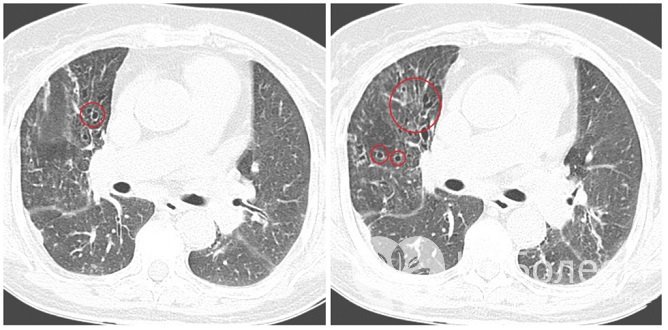

Визуализация бронхоэктазов на КТТерапия бронхоэктатической болезни комплексная: